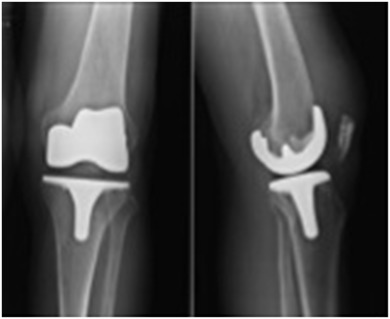

A 55-year-old male presented complaining of chronic knee pain that had worsened over the previous 3 years. This had been treated medically and with physiotherapy for the last year. The treatment included anti-inflammatory medications, two injections with viscosupplementation, and two intra-articular steroid injections, but resulted in no sustained improvement. On physical examination, the left knee was neutrally aligned. There was a mild effusion, with tenderness over the medial and lateral joint lines. The range of movement was from 0° of extension to 120° of flexion; extension was painless, while knee flexion was painful over the terminal 40°. There was no laxity of the collateral or cruciate ligaments. The distal neurovascular examination of the extremities was intact and symmetric. Radiographically, the left knee showed degenerative osteophytic changes and osteophytes in all compartments of both knees, with narrowing and sclerosis of the medial joint space (Fig. 1 ). The patient also had the darkly stained sclera and pinnae characteristic of ochronosis (Fig. 2 ).

Fig. 1

Fig. 1.

Preoperative radiographs showing osteoarthritic changes.